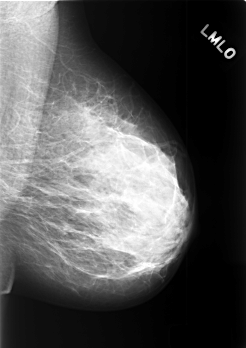

C_0421_1.LEFT_MLO

LEFT_MLO LINES 5560 PIXELS_PER_LINE 3936 BITS_PER_PIXEL 12 RESOLUTION 50 NON_OVERLAY